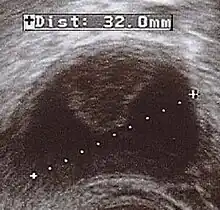

| Corpus luteum cyst with bleeding. Fresh blood is anechoic (black). A protrusion of coagulated blood (lighter in color) can also be seen in the top of the cyst. | |